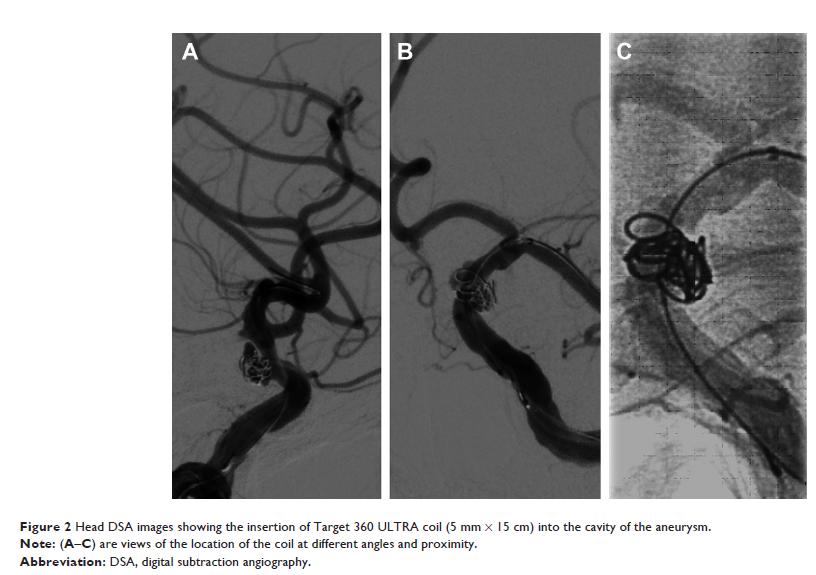

Case Report

- 作者:Ning Xu, Hao Meng, Tianyi Liu, Yingli Feng, Yuan Qi, Honglei Wang

- 期刊:Neuropsychiatric Disease and Treatment